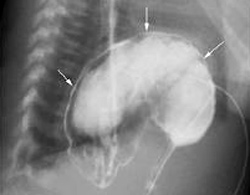

Dạ dày chui lên lồng ngực bệnh nhân. Ảnh: B.V

Tại bệnh viện, diễn tiến của bé ngày càng xấu, bụng trướng to, ói nhiều hơn. Chẩn đoán qua hình ảnh cho thấy có hiện tượng dạ dày dãn to, ứ đọng dịch. Kết quả chụp phim còn phát hiện, dạ dày của bé phần dưới bị xoắn lên cao và một phần chui lên lồng ngực.